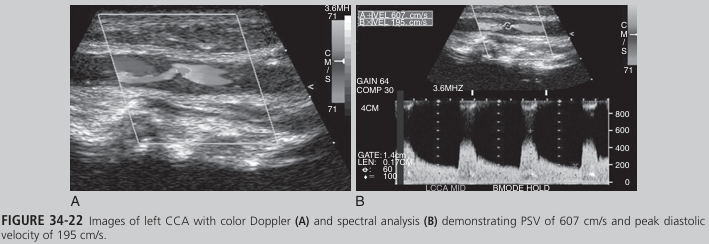

A 67-year-old man developed acute blindness in the left eye while at work. When he arrived at the hospital, he claimed to have got ten lost in the elevator. Staff noticed he appeared uncoordinated and confused and had trouble expressing himself. A carotid sono gram demonstrated the finding in Figure 34-22 (see Color Plate 53) in the left CCA. The left vertebral artery was found to be occluded. After 3 days, the patient’s symptoms completely resolved. What do these findings suggest?

the man was experiencing a reversible ischemic neurologic deficit